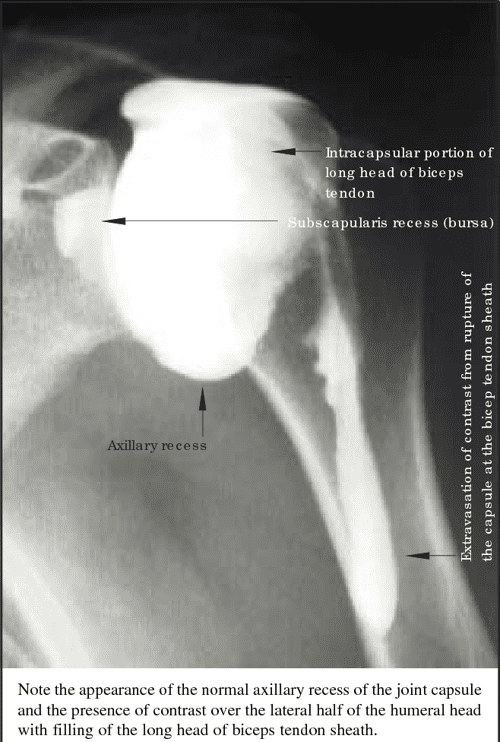

Frozen Shoulder Radiology Melbourne Melbourne Radiology Treatment For Frozen Shoulder Hydrodilatation Another treatment, called hydrodilatation, involves injecting the shoulder with glucocorticoid and saline to expand the. Nonsurgical treatments include nonsteroidal anti. The most effective treatment for adhesive capsulitis is uncertain. Treatment options for frozen shoulder include physiotherapy, injections, hydrodilatation, manipulation under anesthesia,. The focus of treatment is to control pain and restore motion and strength through physical. The present systematic review. Treatment For Frozen Shoulder Hydrodilatation.